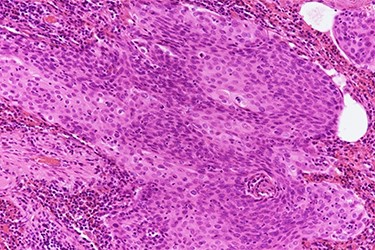

Histopathologic slide shows keratin pearls of squamous cell carcinoma (hematoxylin and eosin stain, 200× magnification).

A 80-year- Japanese woman first visited our hospital in March 2017 with several neurological symptoms such as headache, incontinence, wobble and consciousness disorder (Glasgow Coma Scale: 14). She was a smoker (from 18 to 80 years of age, one pack per day, Brinkman Index: 1240) and had no family history of malignancies. Brain magnetic resonance imaging (MRI) revealed hyperintense signals on T2-weighted (Fig. 1A) and fluid attenuation inversion recovery (FLAIR) images at the splenium of the corpus callosum (Fig. 1B). These findings were compatible with limbic encephalitis. A cerebrospinal fluid analysis showed inflammation with negative cytology, and an electroencephalogram demonstrated normal study. Because PLE due to malignant tumor was suspected, a systemic examination was performed. Chest computed tomography (CT) detected a nodule with an irregular margin measuring 17 × 14 mm in size at the subpleural area of the left upper lobe S3 of the lung (Fig. 2). The enhanced systemic CT and brain MRI detected neither regional lymph node swelling nor distant metastases, and then it was classified as clinical stage T1bN0M0 according to the eighth edition of the TNM classification by International Association for the Study of Lung Cancer (IASLC). Her conscious level was worsening (Glasgow Coma Scale: 5). After obtaining informed consent, lung partial resection was performed via video-assisted thoracic surgery (VATS). The permanent pathological examination revealed squamous cell carcinoma (keratinizing type) (Fig. 3), and it was classified as pathological stage T1bN0M0. Anti-Hu antibody, one of onconeural antibodies, was investigated as part of the workup for PLE, but the result was negative. Her post-operative course was uneventful, but she died 50 days after surgery caused by the rapid progression of encephalitis.